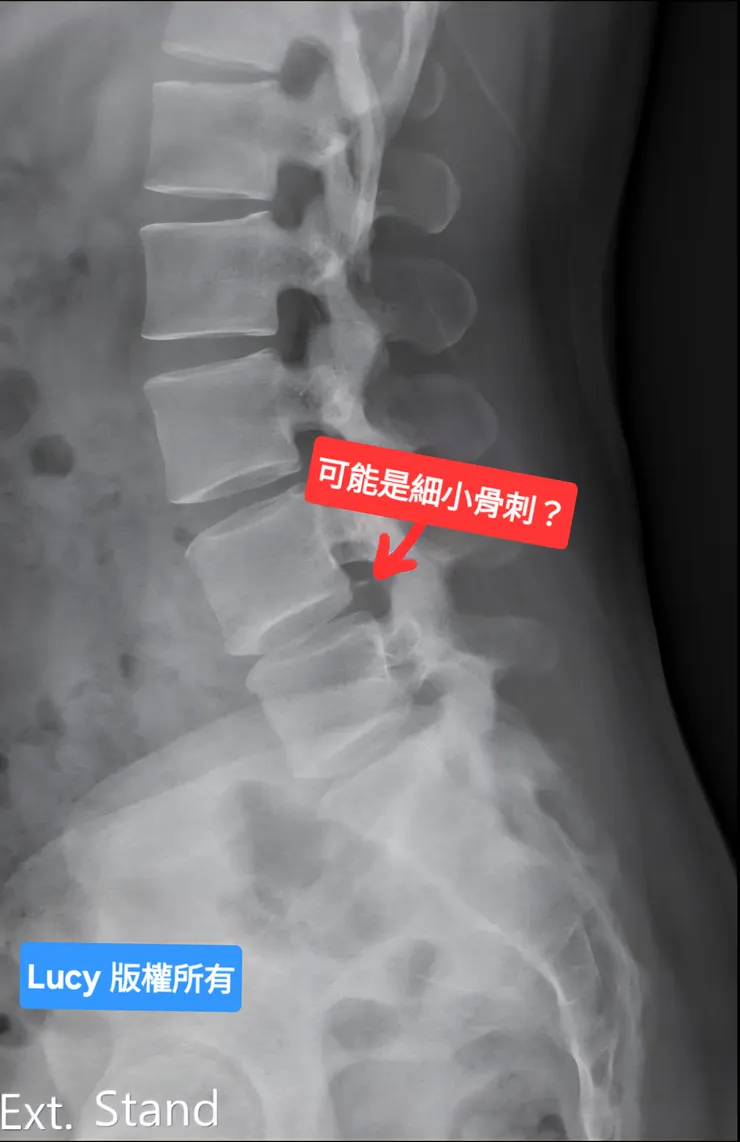

我試探性地問道:「發燒是否可能是腰部發炎引起的?能否安排做核磁共振進一步檢查?即使需要自費,我們也願意。」但醫生不為所動,只是不耐煩地說:「X 光看起來很正常,可能只是長了細小骨刺,沒必要照核磁共振。」說完,便要我去看感染科。

X 光影像醫生說疑似有長小骨刺?